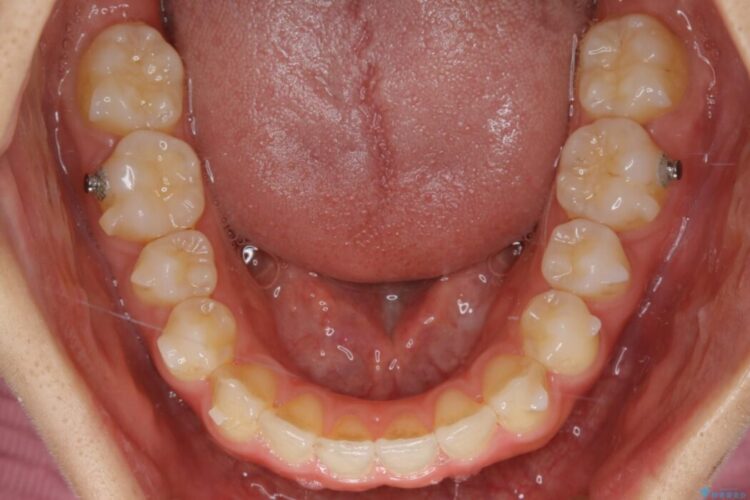

- 矯正装置:インビザライン ライトパッケージ

検査したところ叢生度合いから抜歯をせずとも治療が可能と判断しましたので、インビザラインでの非抜歯矯正を行う方針としました。

治療後写真を見ても歪みが解消され、歯列弓がきれいに整ったのが分かると思います。インビザラインをしっかりと装着されていたこともあり、矯正としては短期間の治療となりました。